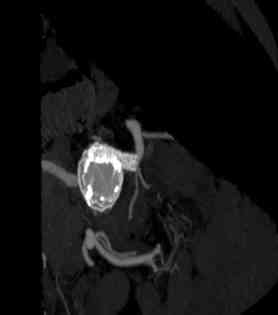

Figura 3. Angio-TC de control: Corte axial en lado izquierdo y su reconstrucción en 3D en lado derecho donde se demuestra exclusión del aneurisma con permeabilidad tanto de las chimeneas renales como del resto de arteriales viscerales, sin endofugas ni desplazamientos de la prótesis.